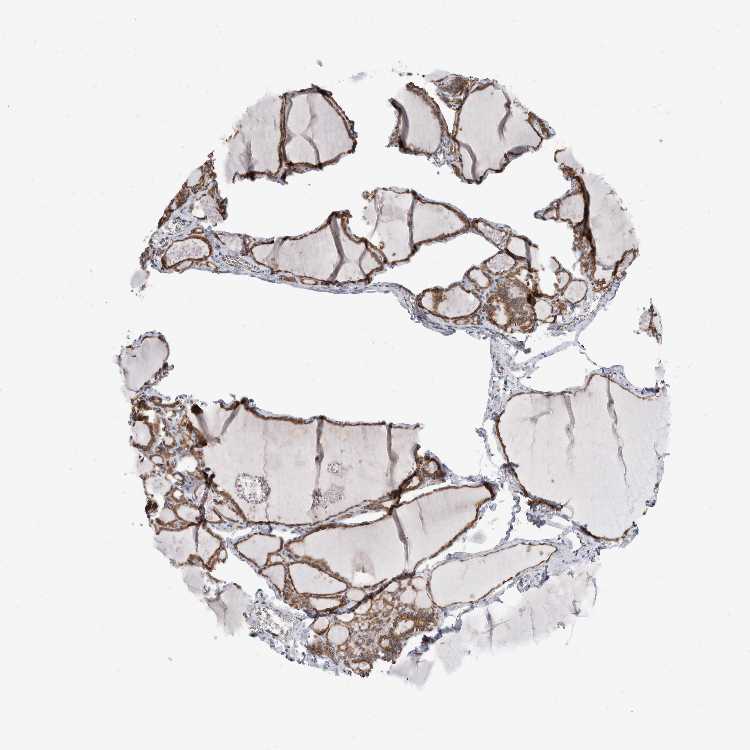

THYROID GLAND - Antibody stainingi

Antibody staining in the annotated cell types in the current human tissue is reported as not detected, low, medium, or high, based on conventional immunohistochemistry profiling in selected tissues. This score is based on the combination of the staining intensity and fraction of stained cells.

Each image is clickable and will lead to virtual microscopy that enables deeper exploration of all samples and also displays staining intensity scores, fraction scores and subcellular localization as well as patient and tissue information for each sample.

Antibody HPA023892

Glandular cells High